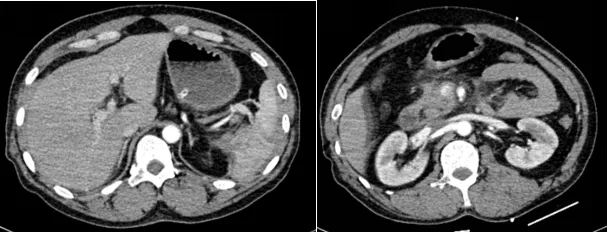

胰周、脾周大量渗出、血肿形成